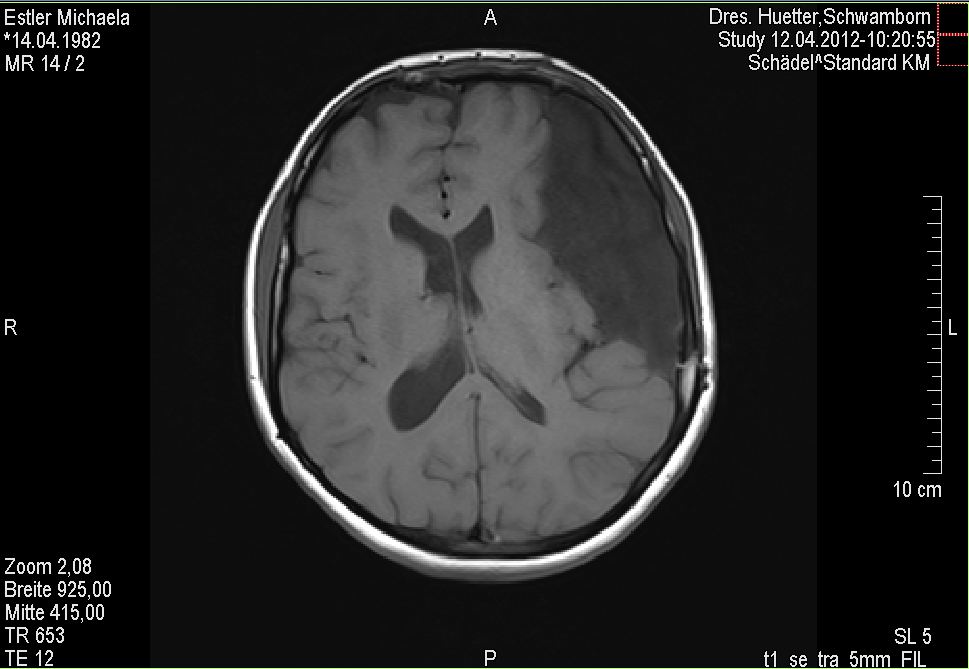

Es war MRT Tag heute. Für diejenigen unter Euch, die es noch nicht wissen sei an dieser Stelle gesagt, dass ich alle zwölf Wochen ein MRT meines Kopfes erstellen lassen muss, damit ich immer weiß, was mein Untermieter in meinem Kopf so schönes treibt, ob er weiterhin Wachstumsambitionen hat usw. Tja und bei solch einer Untersuchung bekommt man ca. nach Hälfte der Zeit einen netten Kontrastmittelcocktail gespritzt, damit manche Dinge auf dem Screening hervorgehoben werden etc. Eigentlich reicht zur Verabreichung dieses Cocktails ein Spritzeneinstichloch in der Armbeuge aus. Aber nun ja, was soll ich sagen? Ich habe es noch nie so wirklich erlebt, dass irgendwer auch auf Anhieb wirklich hinbekommen hat. Und so bin ich bisher jedes Mal mit einigen Einstichlöchern aus der Praxis hinausgelaufen. Ist ja nicht so, dass das überhaupt gar nicht weh tut in der Armbeuge mit so langen Nadeln etc. :haue:

Wie unschwer herauszulesen mag ich diese MRT Tage nicht besonders. Sowieso nicht, wenn dann mein Untermieter auch noch auf den Bildern fast die halbe Hirnfläche ausfüllt. Ich hasse meinen Untermieter echt übelst, aber wie schon längst bekannt werde ich ihn auch in meiner ab Samstag beginnenden neuen Lebensdekade behalten müssen.